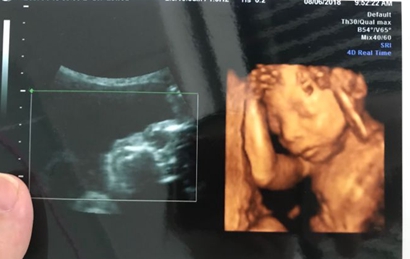

一:在彩超单上会印,顶头最右边有两行字,是英文字母和数字组成的,第一行是日期,第二行是时间,如果第一行是M开头,那就是male男,如果是F开头就是female女,第二行打头的T是时间的意思。

三:彩超单上很小英文字母Qual high 1是女孩,2是男孩。